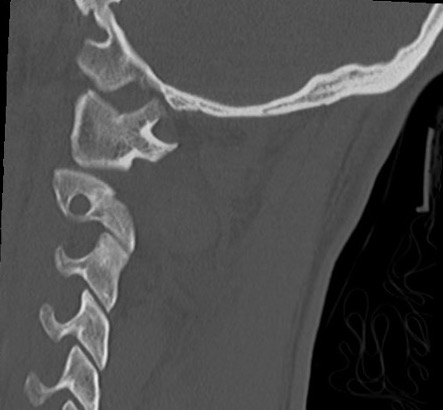

Xray / CT measurements

Frequently missed on xray

Basion-Dens Interval / BDI

- basion to tip of dens

- vertical displacement > 12 mm

Basion-Axial Interval / BAI

- basion to posterior border ondontoid

- anterior displacement > 4 mm